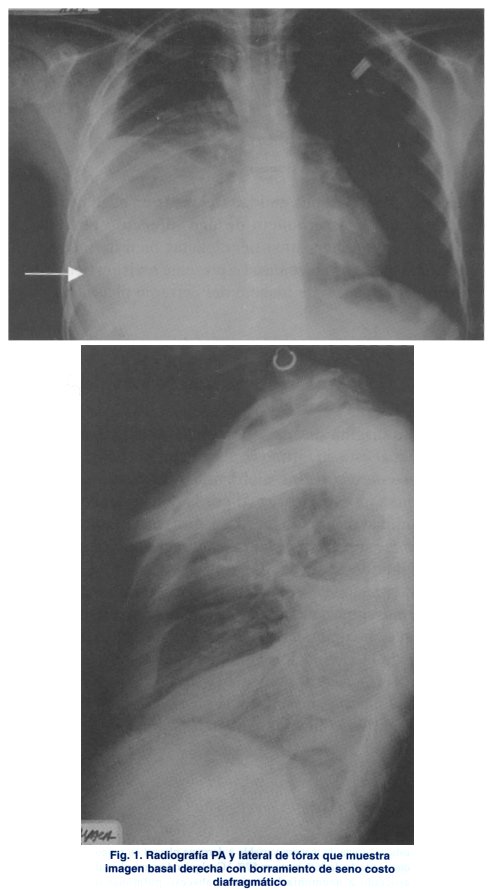

Radiología. Las proyecciones solicitadas deben ser antero-posterior y lateral. El primer hallazgo es el borramiento del ángulo costo frenico, en los niños se requiere mas de 40cm3 de líquido para que pueda verse radiológicamente. Con las proyecciones en decúbito lateral se pueden revelar pequeñas cantidades de líquido pleural, no visibles en proyecciones frontales.